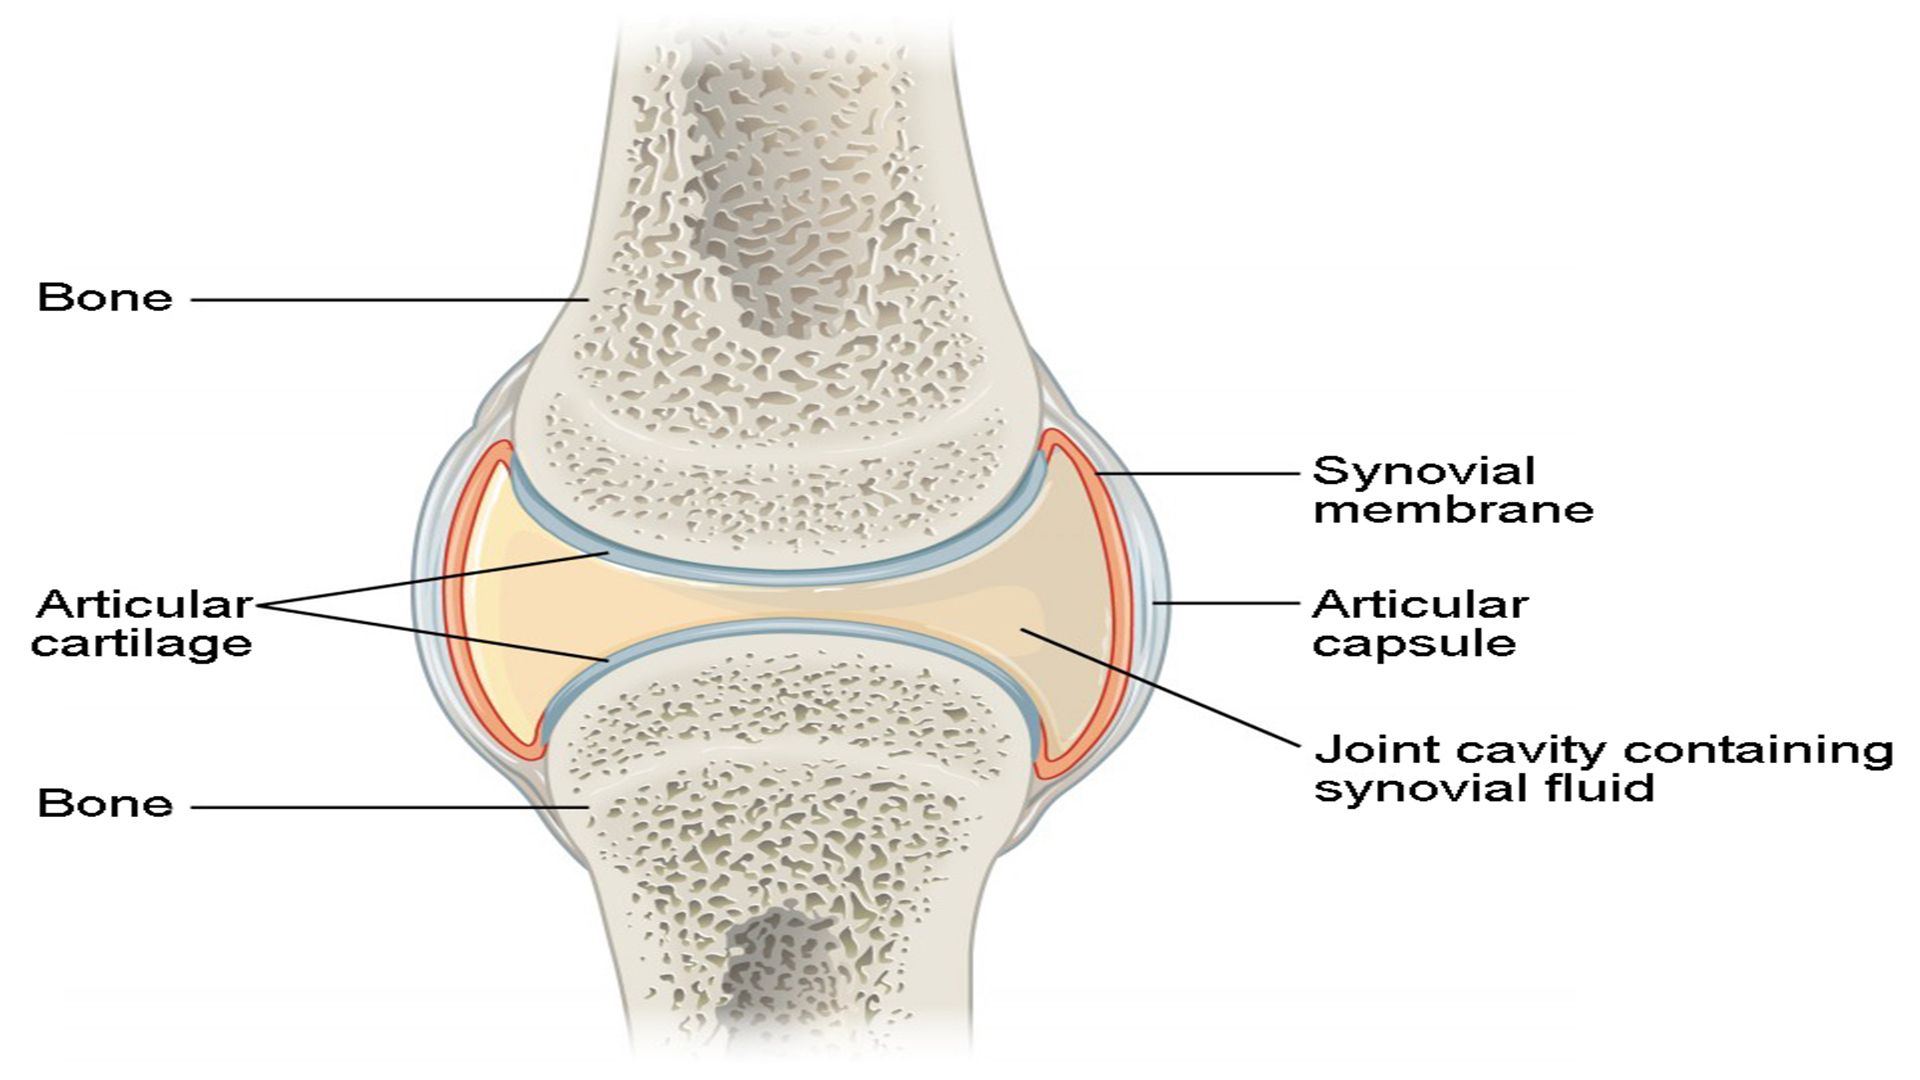

Суставная Жидкость и Головка Сустава: Обзор и Здоровье